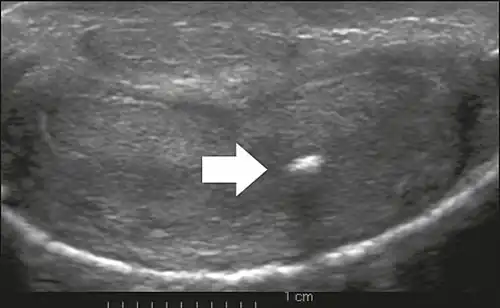

Figure 6: Transverse ultrasound of the penis, in a ventral view, in the middle portion of the penis. Note the echoic image with posterior acoustic shadowing, corresponding to calcification (arrow), in the left corpus cavernosum.[1]